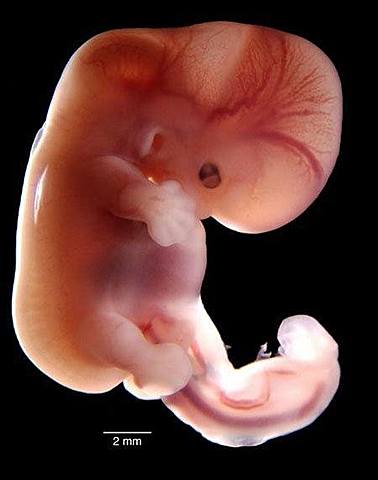

• 10

TERCERA SEMANA

• Gastrulación

11

Gastrulación

El disco bilaminar se transforma en trilaminar (ectoderm, mesodermo, endodermo)

• Nerulacion

12

Nerulacion

Formación del tubo neural que formara el sistema nervioso central

• Desarrollo de somitas

14

Desarrollo de somitas

Son bloques de independientes del mesodermo que darán origen a celulas que formaran, vertebras, costillas, y piel